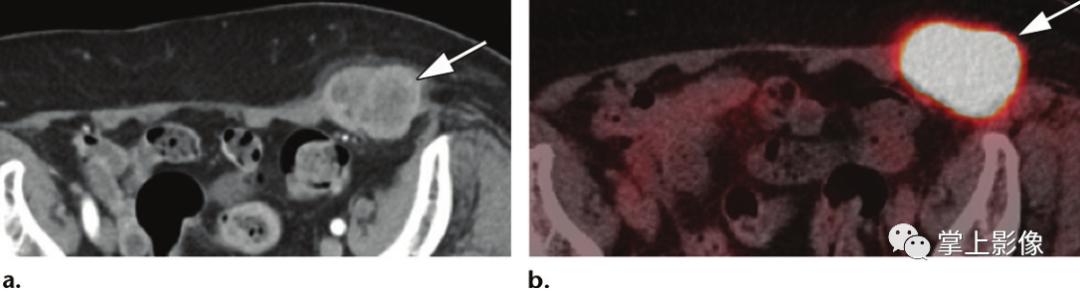

原发性皮肤淋巴瘤,55岁男性,无相关病史,前腹壁有明显肿块。(A)轴位CT图像显示强化肿块(箭头)。(B)轴位融合PET/CT图像显示FDG亲和力高(箭头)。病理结果为B细胞淋巴瘤